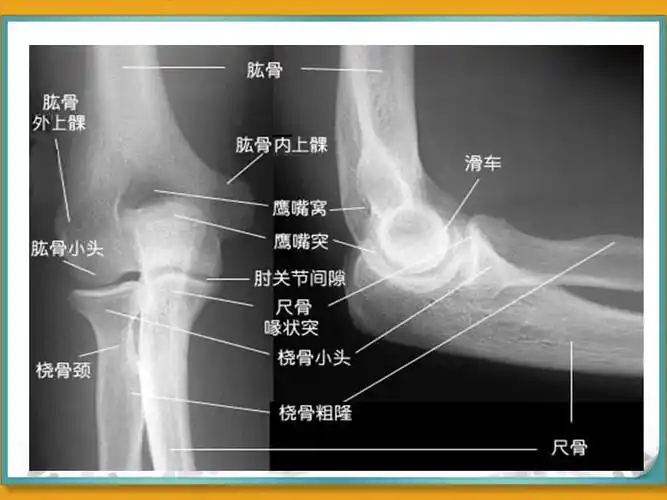

肘关节脱位ppt

标准肘关节正侧位片图,人体结构 #医学影像 - 抖音

2019--8-26 肘关节x线解剖学

肘关节